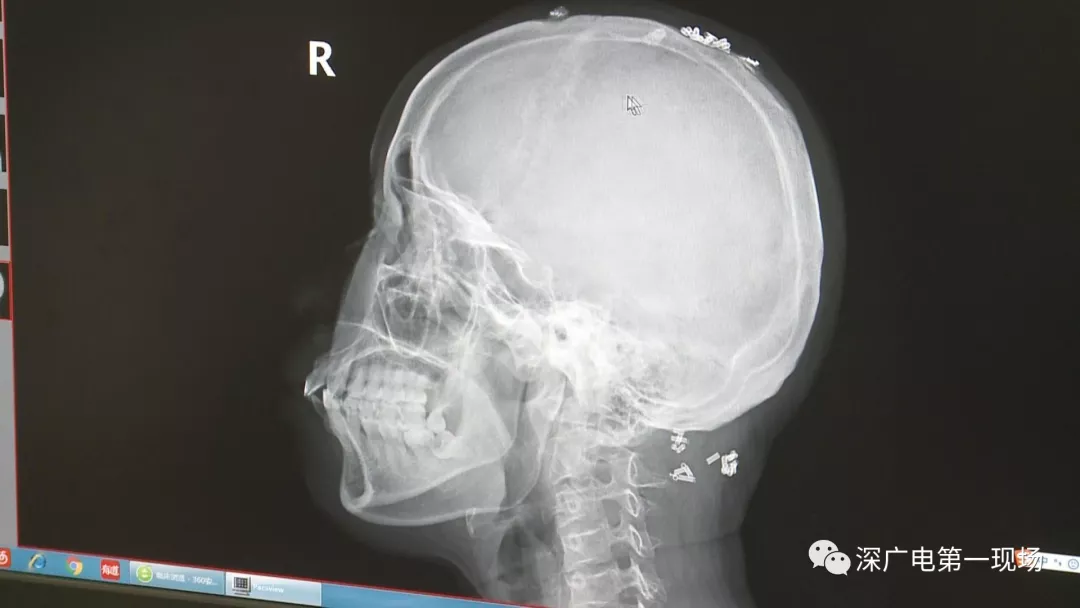

深圳一女子全身被植入彈簧圈,數(shù)量多到驚人!竟是為治這病…

彈簧圈已“寄生”三年

部分形成包塊難以取出

據(jù)了解,這位患者周身的彈簧圈已經(jīng)固定了三年多,因?yàn)榛颊吒杏X治療效果不好,就來(lái)深圳求醫(yī)。